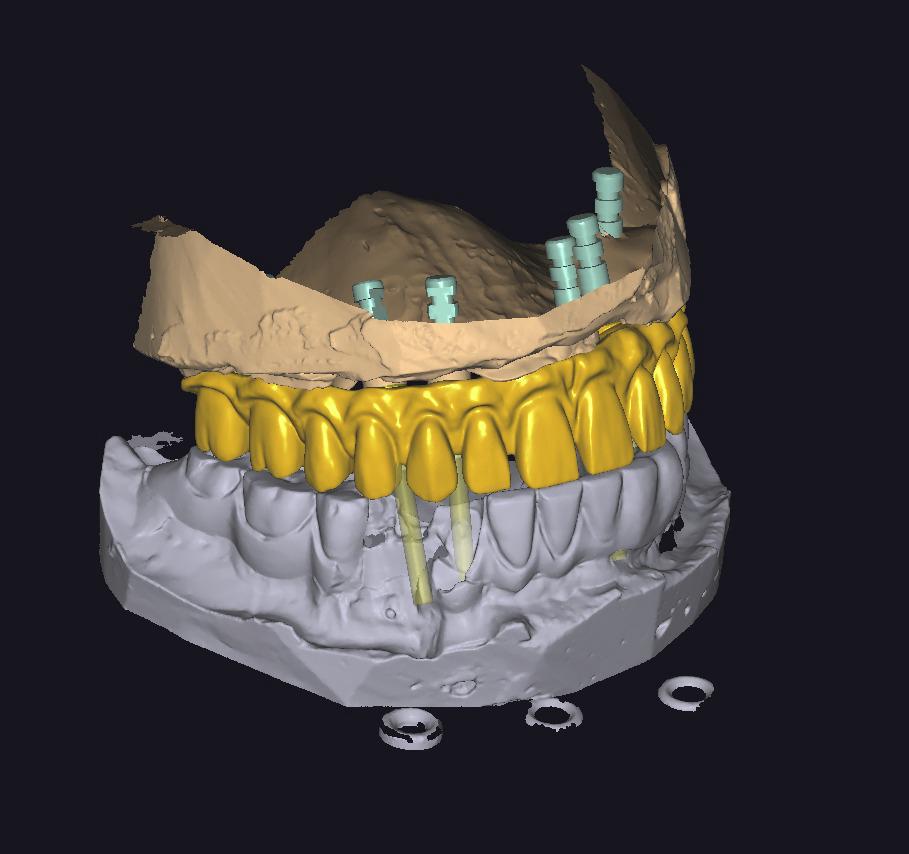

IMPLANT USTU ZIRKONYUM

IMPLANT USTU ZIRKONYUM ALT YAPI

MONOLITIK IMPLANT USTU ZIRKONYUM & ÜSTTEN ViDALI ZİRKONiUM

MULTILAYER IMPLANT ÜSTÜ ZIRKONYUM & ÜSTTEN VİDALI ZIRKONYUM

HYBRID PROTEZLER

HYBRID CAM CAM CrCo & TITANYUM PORSELEN BITIM

CAD CAM CERRAHI PLAK